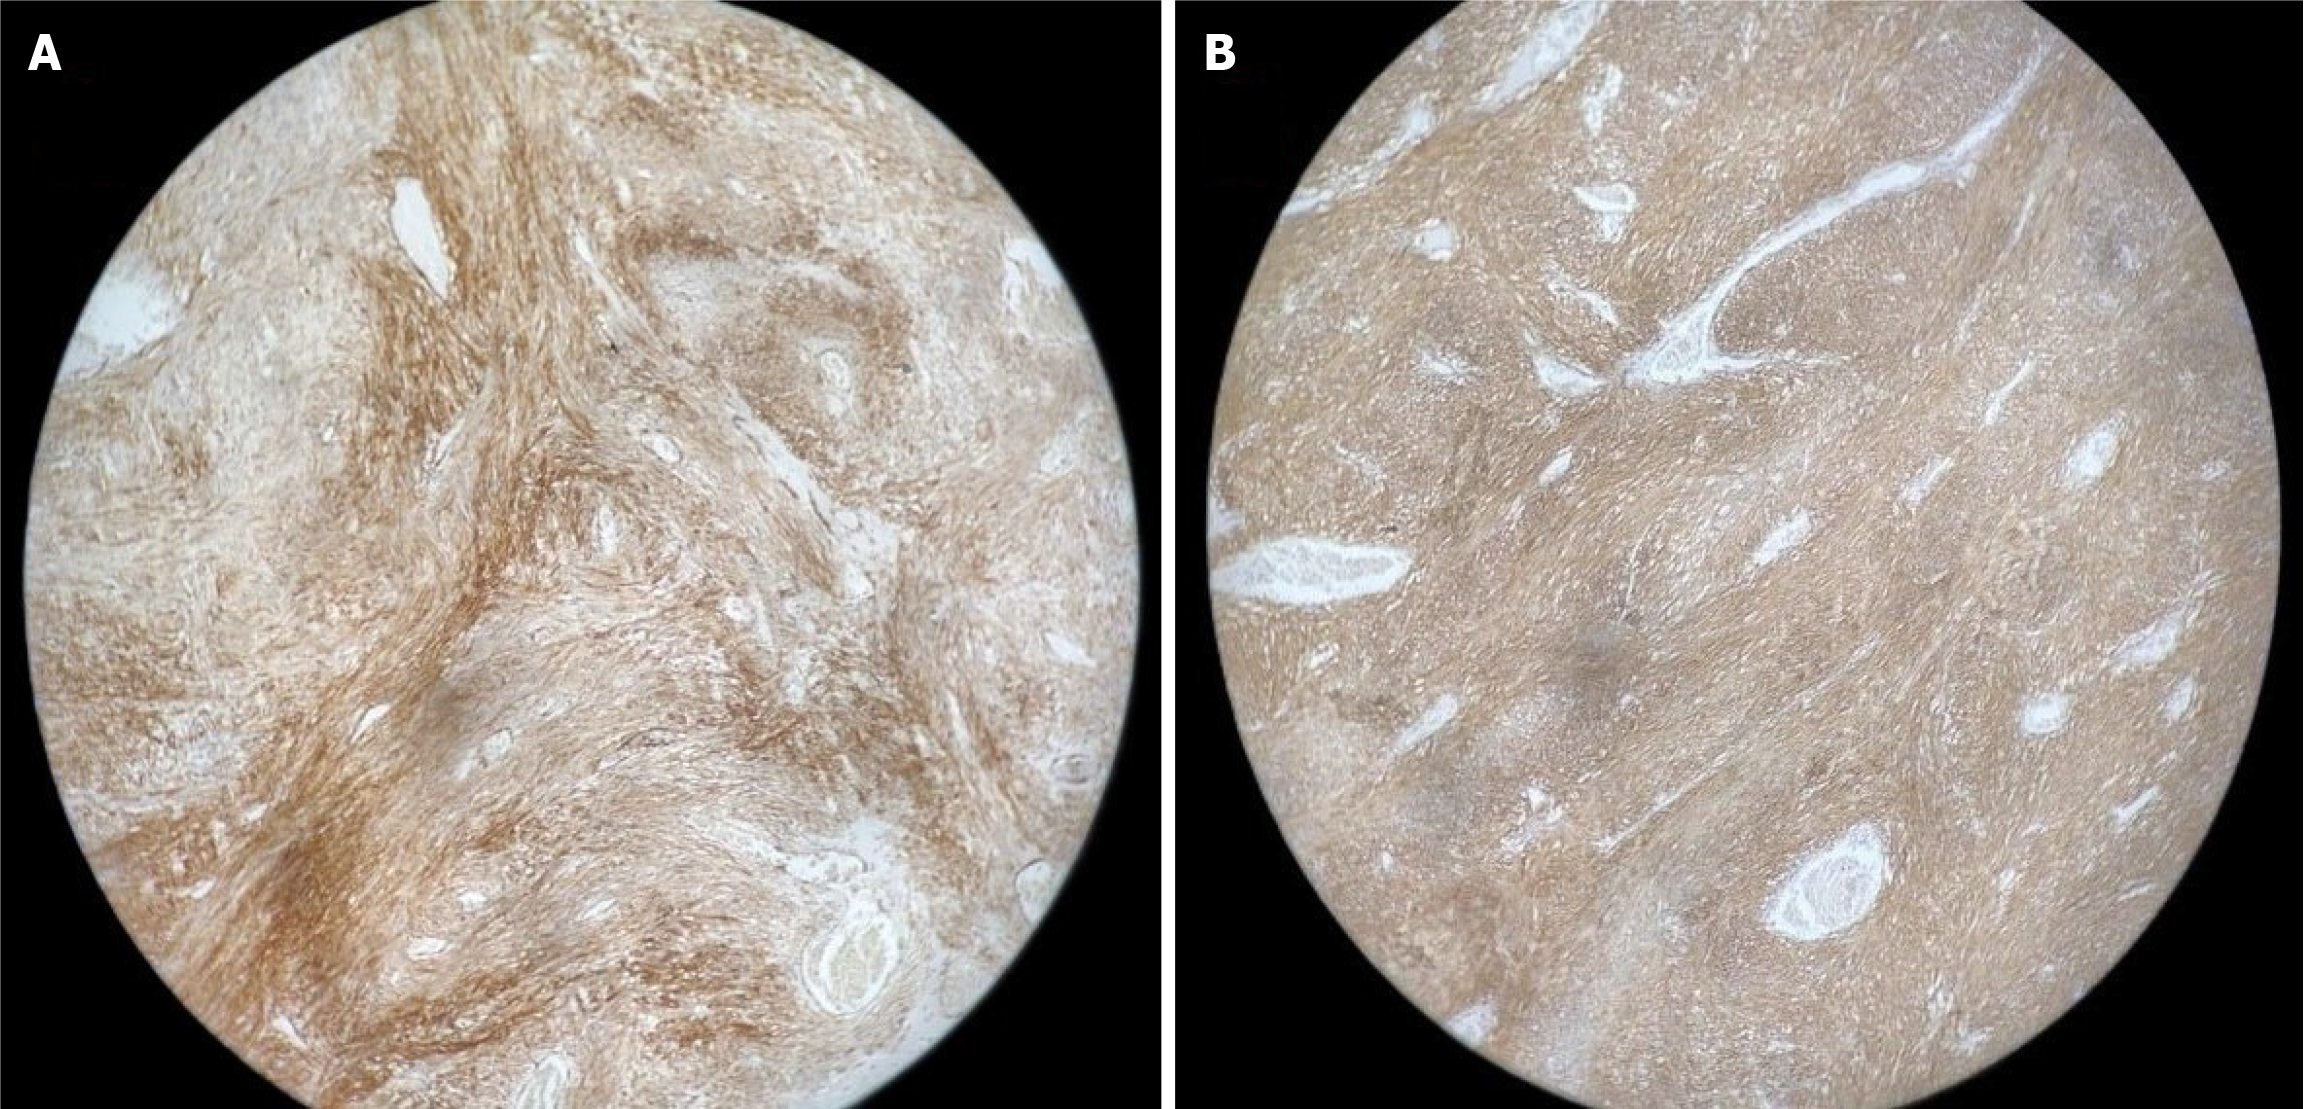

Figure 3 Immunohistochemical profile of postoperative jejunal specimen showing diffuse immunopositivity.

A: CD117; B: DOG1 markers.